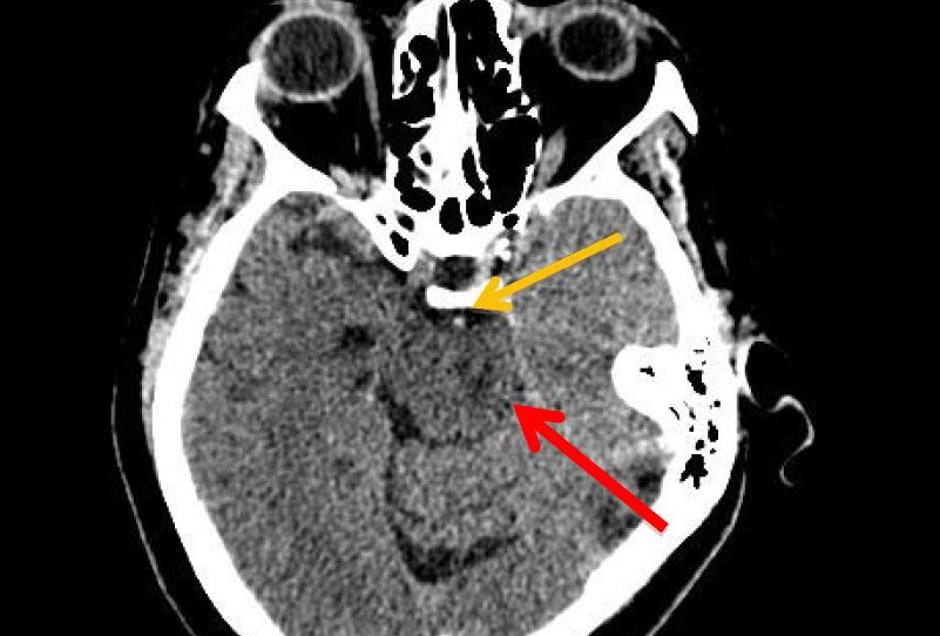

Kot navajajo zdravniki, je doživela sindrom zaklenjenosti, ki je redek pojav po možganski kapi. Ekipa zdravnikov z Medicinske fakultete Univerze v Marylandu verjame, da je imela ženska štiri dni po uživanju kokaina zapoznelo možgansko kap. Zaradi tega je njen primer prvi te vrste v znanstveni literaturi.

Sindrom zaklenjenosti je redka možganska motnja, ki povzroči popolno paralizo vseh mišic, razen tistih, ki nadzorujejo gibanje oči. Trpeči so zavestni, vendar ne morejo govoriti ali se premikati. Običajno je prizadeta njihova kognitivna funkcija.

Povzroči  ga poškodba možganskega debla, ki vsebuje živce, ki prenašajo informacije na druge dele telesa. Takšna poškodba se običajno pojavi zaradi pomanjkanja krvnega pretoka ali krvavitve po travmi. Bolniki ne morejo žvečiti, pogoltniti, govoriti ali se premikati, razen oči, vendar lahko vidijo in slišijo. Večina prizadetih je na postelji in je odvisna od nege.